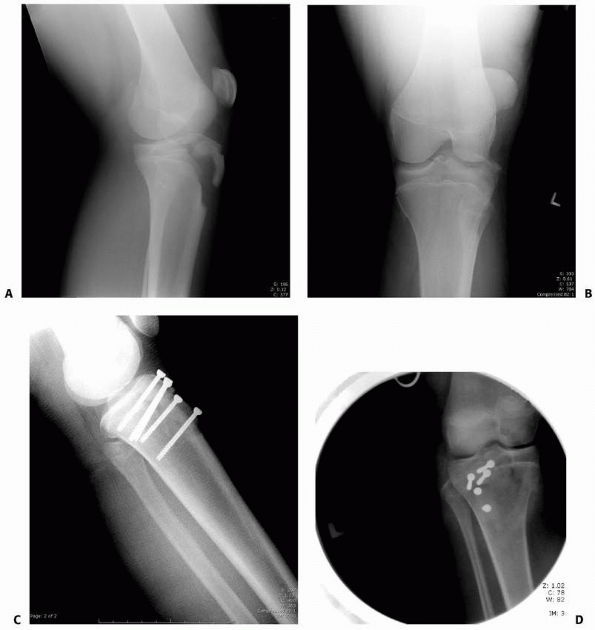

![]() |

FIGURE 23-16 Five-year-old boy hit by car with fracture of the distal femur. A. AP radiograph of minimally displaced Salter-Harris type IV fracture of the distal femur. B.

AP radiograph of healed fracture. From this view, it is difficult to determine if injury to the physis has occurred, though a central growth arrest was suspected. C. MRI shows a central growth plate injury probably did occur, although this did not result in formation of a bony bar or growth arrest. (Courtesy of Robert Kay, MD, Los Angeles, CA.) |